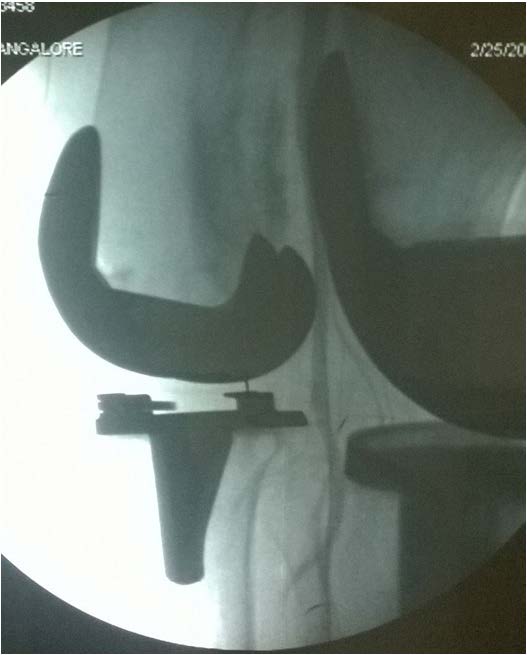

Postoperatively Epidural infusion (Bupivacaine 0.125% and Clonidine 2 μg/ml) was started at 6 ml per hour. Night rounds patient was comfortable with epidural analgesia with bilateral equal pulsations in foot. On next day morning patient complained of severe pain in left calf and numbness in left lower limb, mainly below the knee joint and on examination the left dorsalis pedis and posterior tibial artery pulsation were absent with normal left femoral artery pulsation. Postoperative x-ray in both anterior and lateral view was satisfactory. Toes on the left leg were slightly cooler than on the right and capillary refill time was prolonged. Colour Doppler examination was done which revealed no flow at the level of the knee and below [Table/Fig-1]. Vascular surgeon was immediately consulted and patient was subjected to emergency angiogram followed by thrombectomy and fasciotomy by double incision technique under epidural analgesia on the same day (2nd postoperative day) [Table/Fig-2] and patient was shifted to intensive care unit for next two days with intravenous antibiotics plus heparin infusion, post embolectomy angiogram showed good flow [Table/Fig-3]. On 3rd postoperative day patient had good pulsation on periphery.